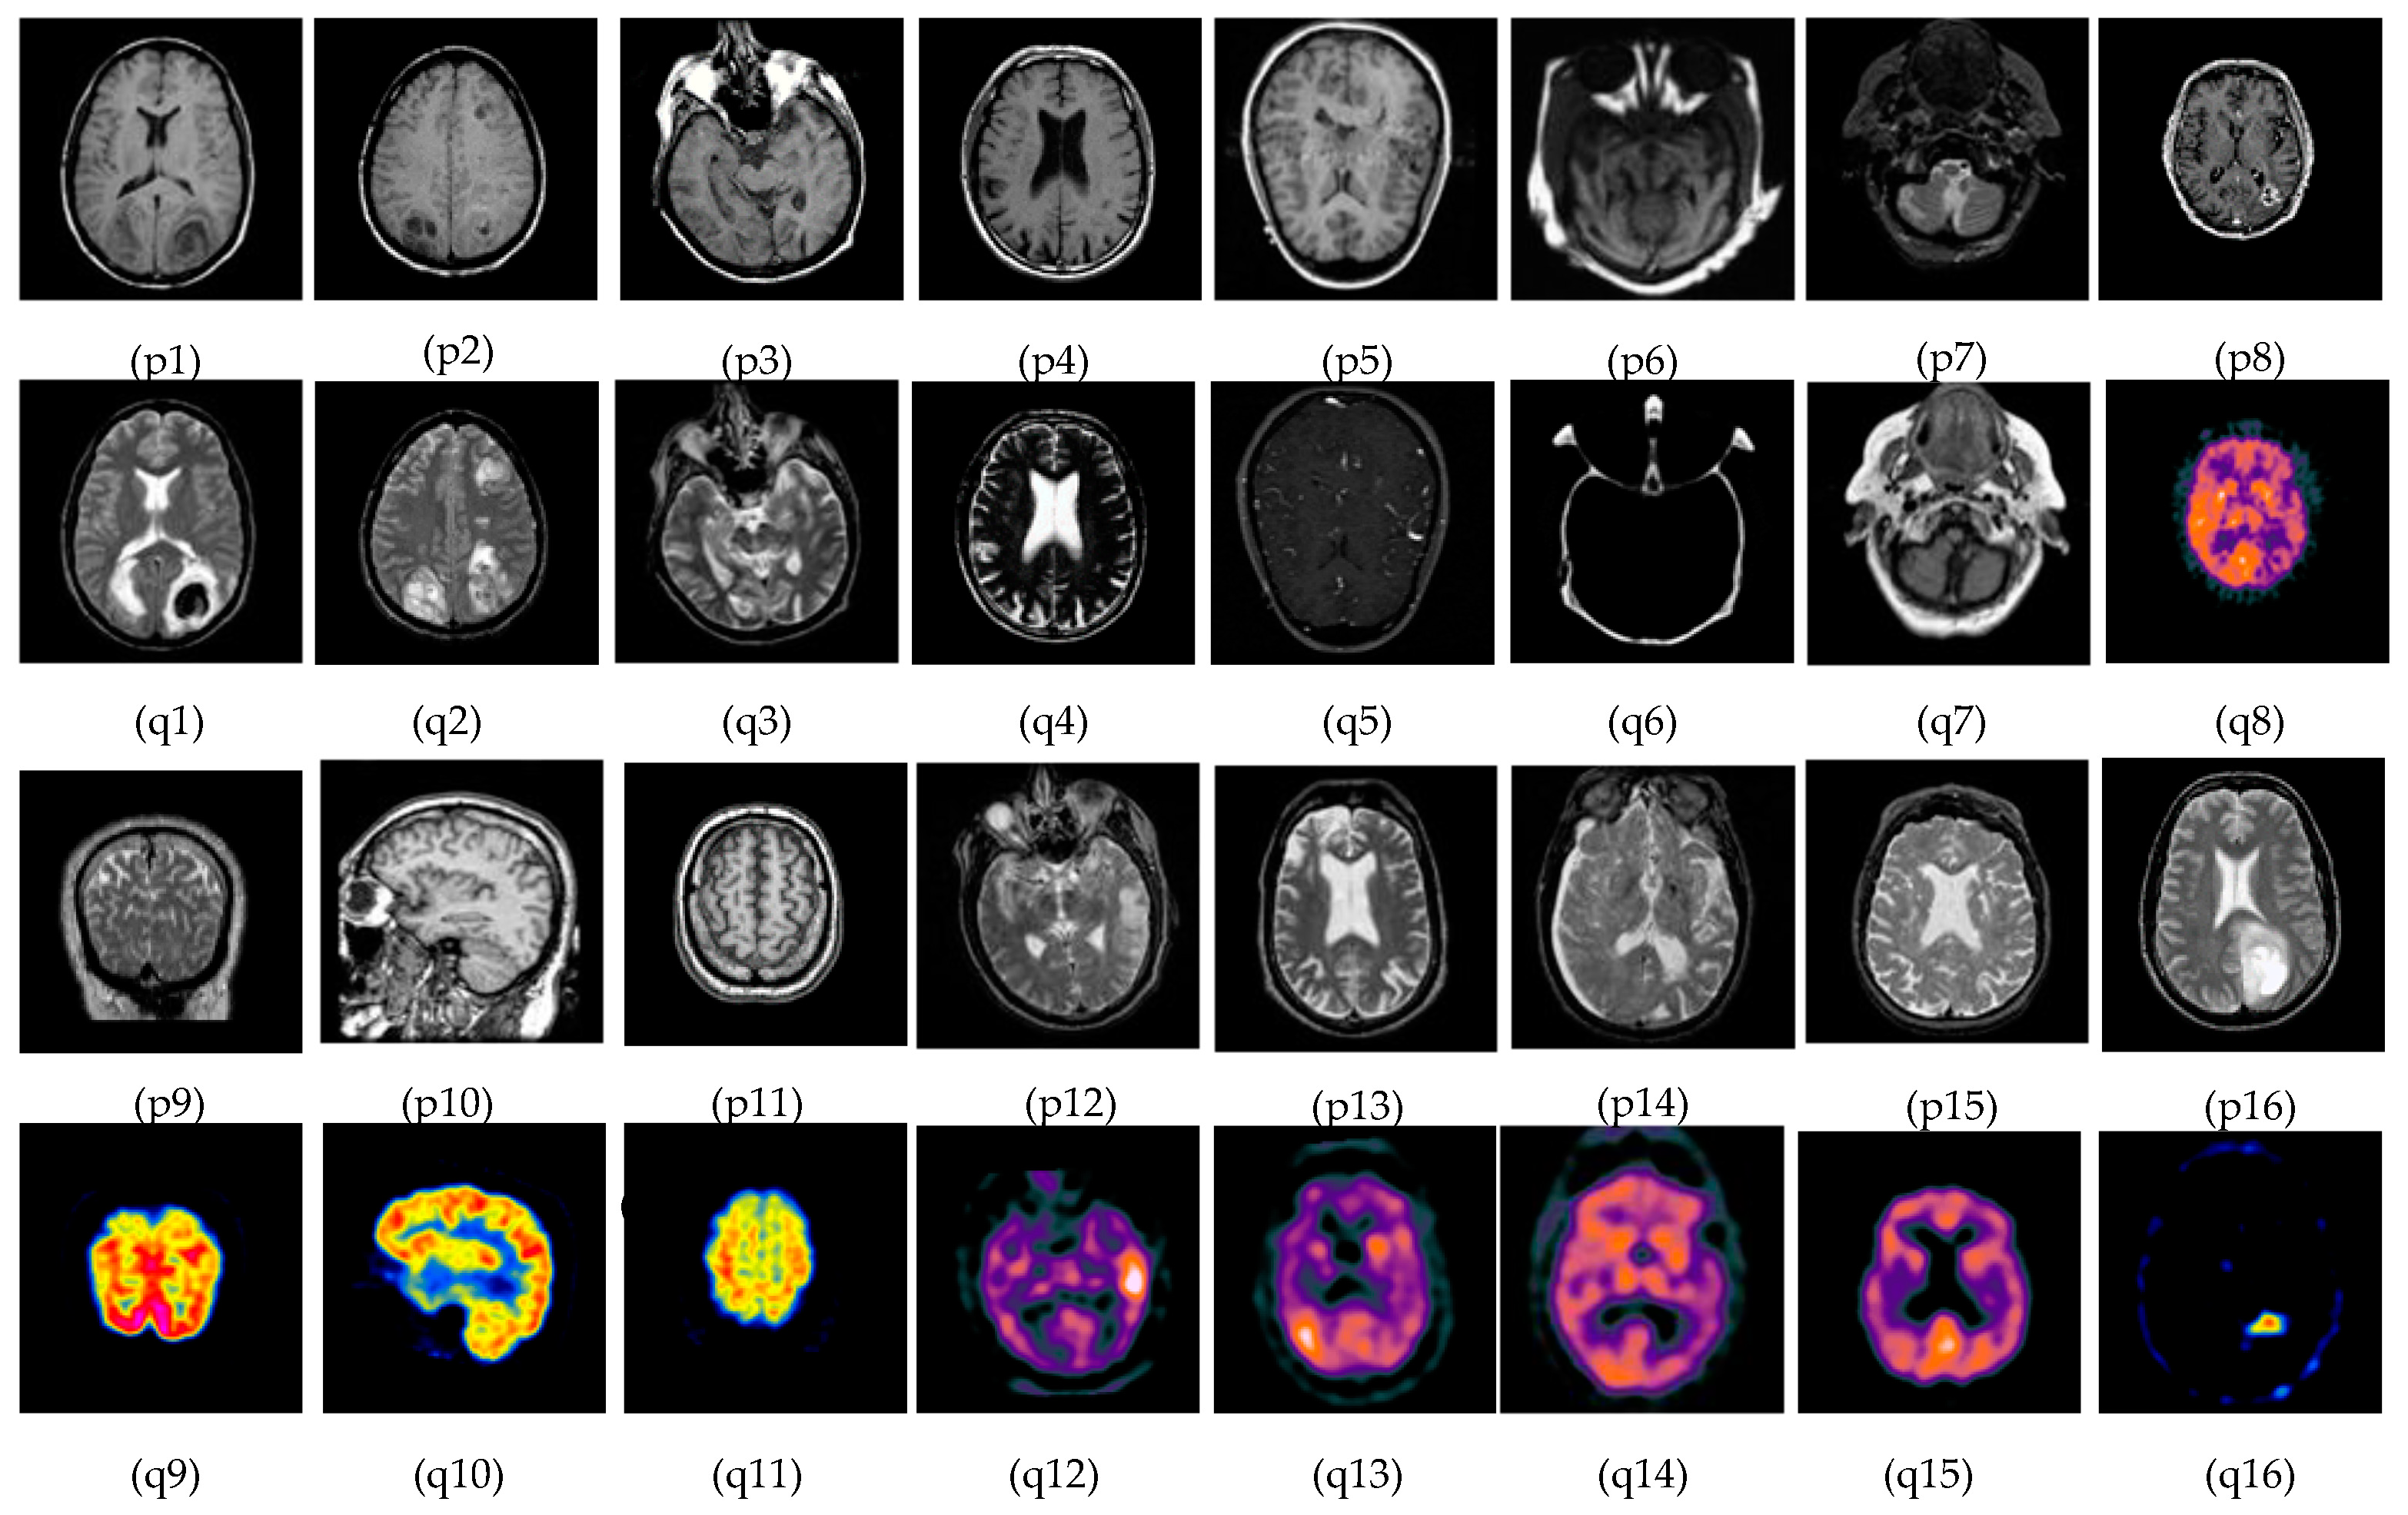

5.1. Subjective-Type Evaluation

- Brain Image. Available online: http://www.metapix.de/examples.html (accessed on 3 February 2020).

- The Whole Brain Atlas. Available online: https://www.med.harvard.edu/aanlib/home.html (accessed on 3 February 2020).